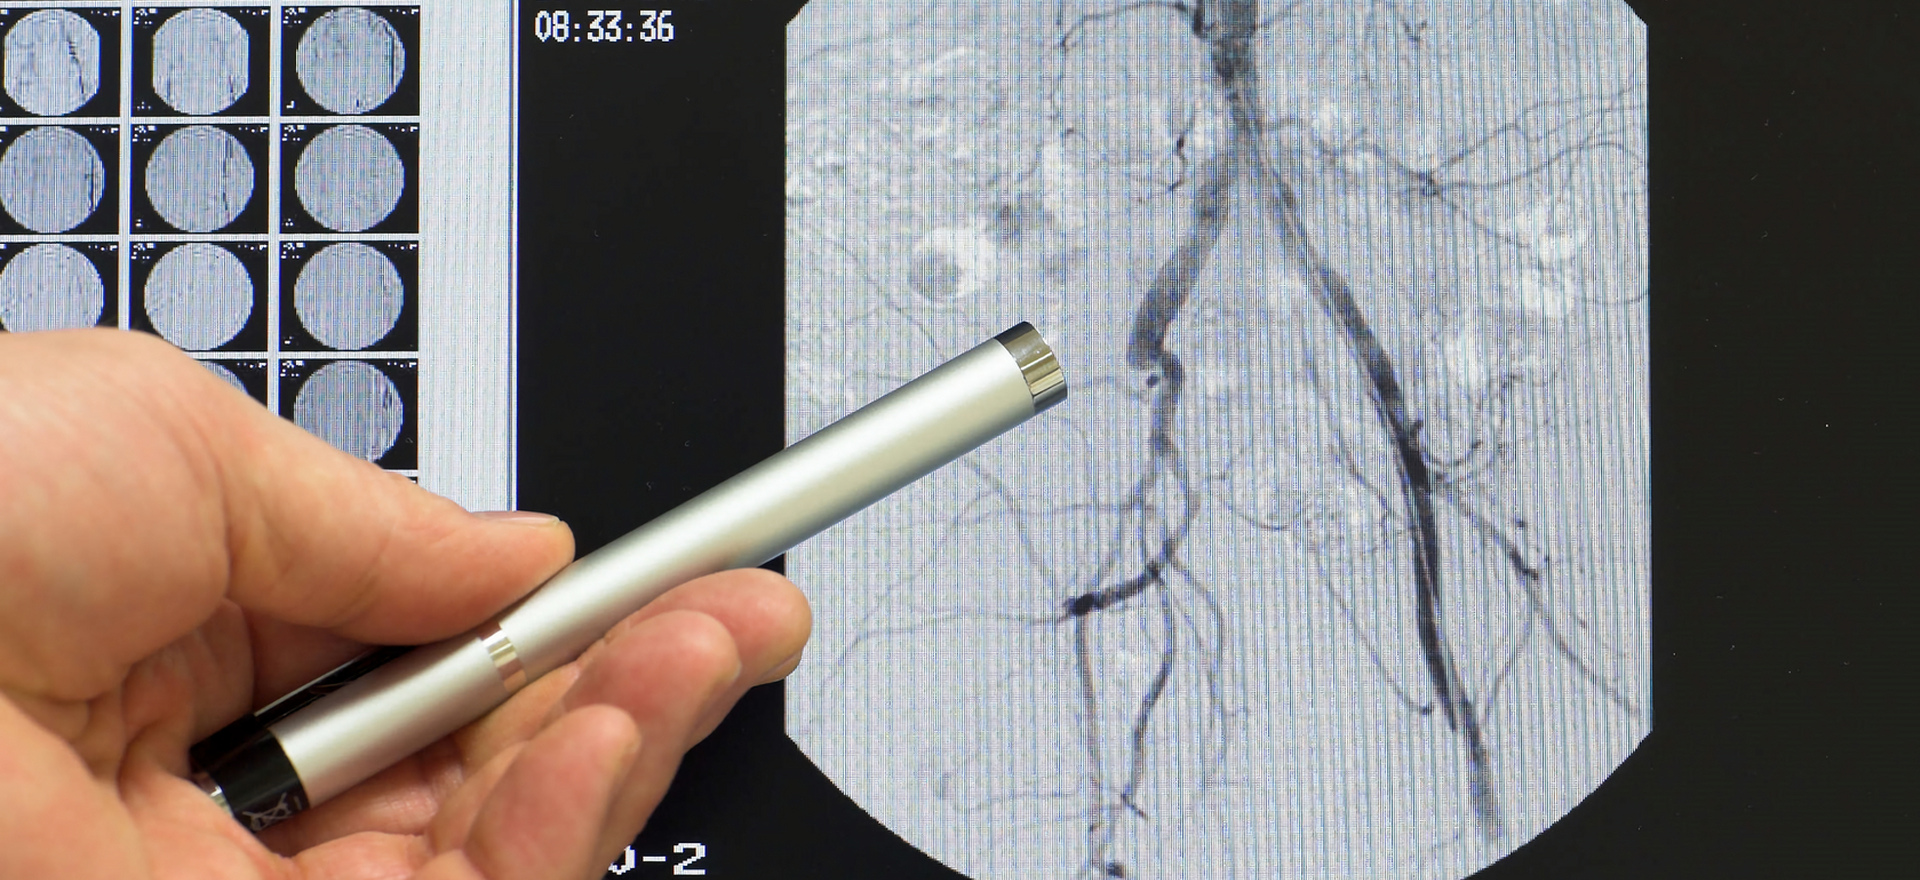

Процедура проводится в рентген-операционной. Пациенту через бедренную или лучевую артерию вводится катетер, который продвигается к коронарным сосудам сердца. Затем вводится контрастное вещество, позволяющее визуализировать сосудистую сеть на ангиографе. Врач анализирует состояние артерий, выявляет суженные участки и при необходимости сразу выполняет стентирование. Исследование длится 30–60 минут, после чего пациенту рекомендуется наблюдение в течение нескольких часов.

Белорусские кардиологические центры оснащены современными ангиографическими комплексами, позволяющими проводить коронарографию с высокой точностью. Опытные специалисты обеспечивают безопасное проведение процедуры и предоставляют детальную интерпретацию результатов.